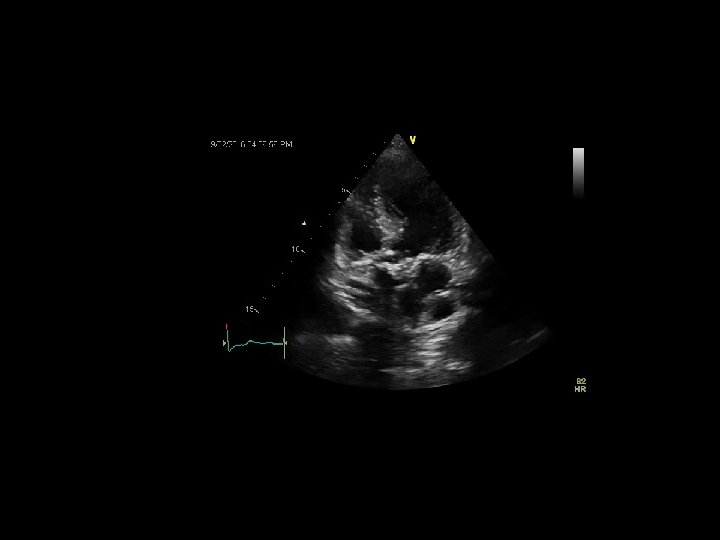

AORTIC STENOSIS Echocardiography 1. Anatomy - short & long axis views (occasionally TEE / 3 D) 2. LVOT diameter – midsystole ; at the site of measurement of LVOT velocity measurement parallel to AV 3. LVOT velocity - apical 4 C / 5 C ; V max / VTI 4. AS jet velocity (CW) – V max; peak and mean gr; VTI 5. SVI 6. DSE ( SOS)

AORTIC STENOSIS Geometric orifice area (GOA) … minimal area by planimetry Effective orifice area (EOA) …. by continuity equation corresponds to venacontracta